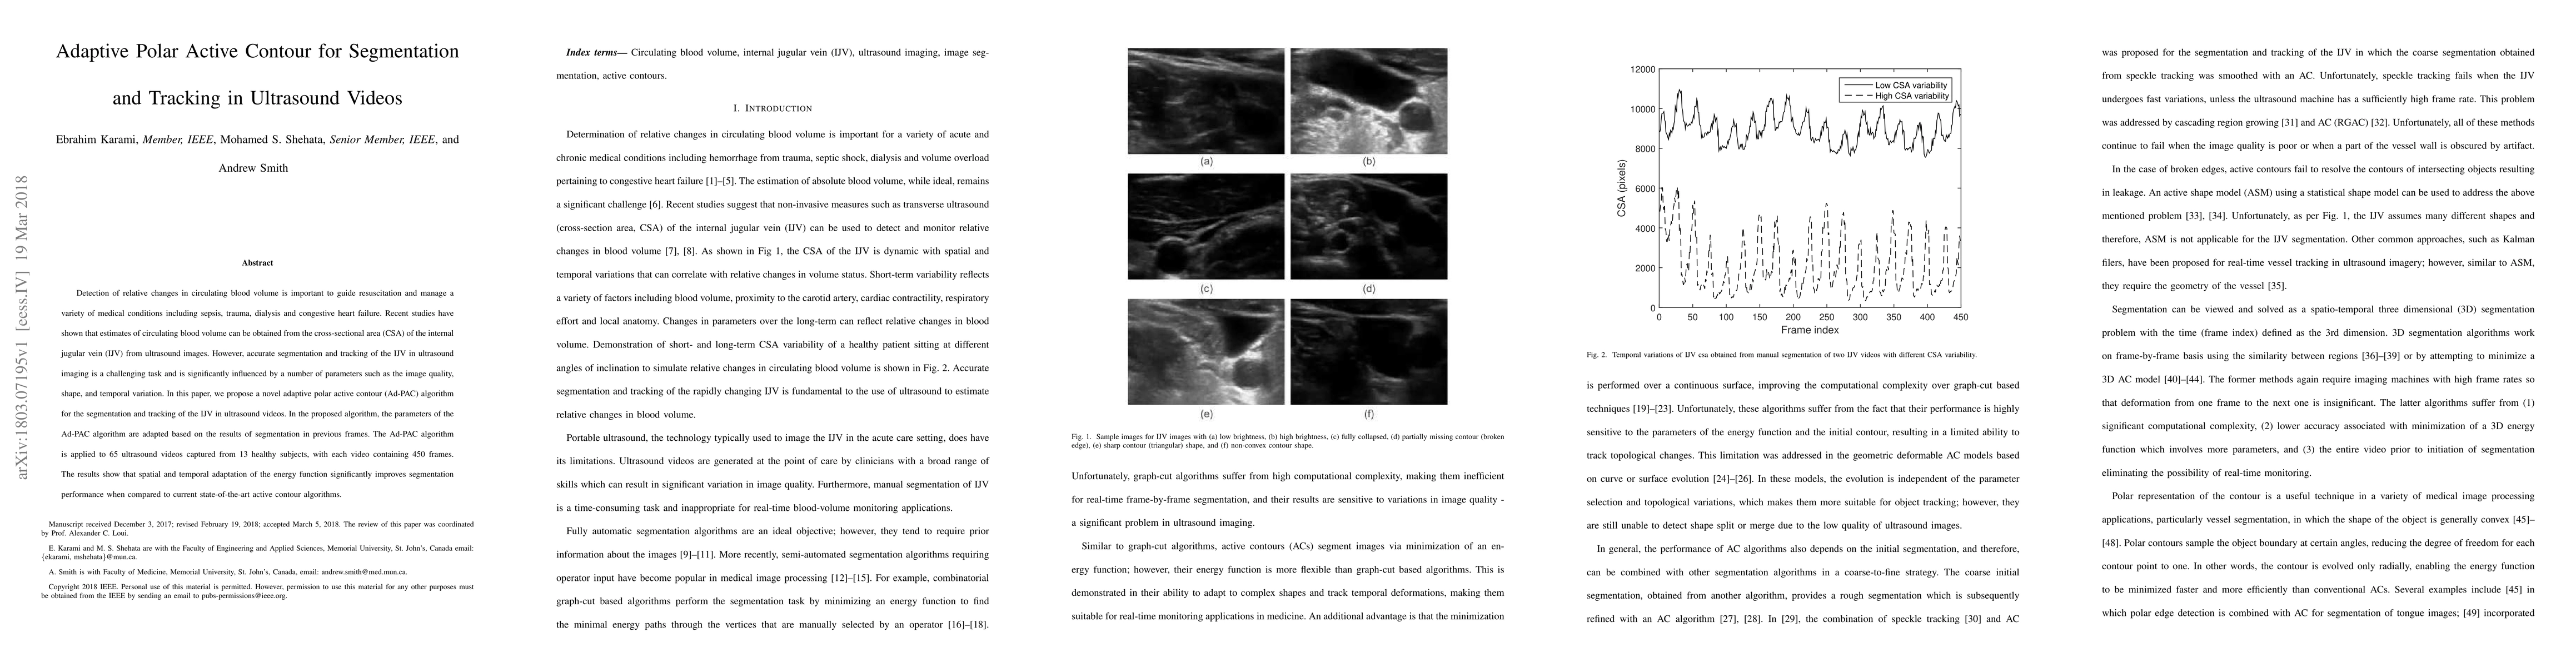

Detection of relative changes in circulating blood volume is important to guide resuscitation and manage a variety of medical conditions including sepsis, trauma, dialysis and congestive heart failure. Recent studies have shown that estimates of circulating blood volume can be obtained from the cross-sectional area (CSA) of the internal jugular vein (IJV) from ultrasound images. However, accurate segmentation and tracking of the IJV in ultrasound imaging is a challenging task and is significantly influenced by a number of parameters such as the image quality, shape, and temporal variation. In this paper, we propose a novel adaptive polar active contour (Ad-PAC) algorithm for the segmentation and tracking of the IJV in ultrasound videos. In the proposed algorithm, the parameters of the Ad-PAC algorithm are adapted based on the results of segmentation in previous frames. The Ad-PAC algorithm is applied to 65 ultrasound videos captured from 13 healthy subjects, with each video containing 450 frames. The results show that spatial and temporal adaptation of the energy function significantly improves segmentation performance when compared to current state-of-the-art active contour algorithms.